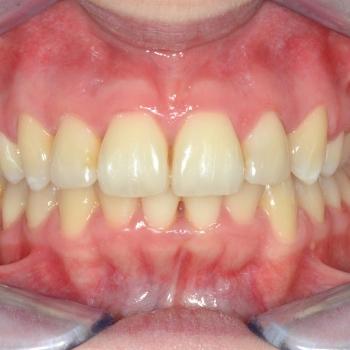

A kezelés végére minden problémát sikerült megoldanunk, a középvonalak korrekcióját leszámítva. Ennek ellenére, mivel a felső középvonal az arc tengelyében helyezkedik el, az esztétikai eredmény nem csorbult és a funkciót sem befolyásolta. A jobb alsó 6-os fog implantációs pótlása a fogszabályozás befejeztével kezdődött meg.

A kezelés időtartama: 2 év 6 hónap